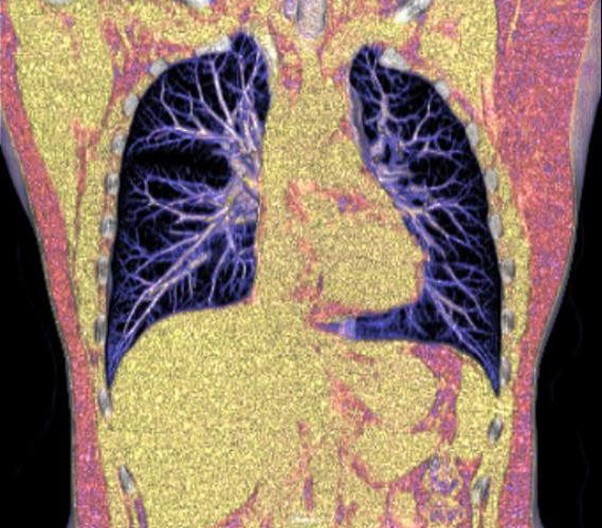

The 1024-pixel image matrix brings superior image clarity (0.6 mm slice thickness) and stimulates the early detection of small lesions, thus improving diagnostic reliance.

ScintCare CT 16 incorporates an entirely digital integrated ScintiStar detector, which was solely developed by MinFound, from material to the whole structure design, based on the technical know-how of our skilled scientific team. The system produces high-resolution images with a low radiation dose and an excellent signal-to-noise ratio.

臨床畫廊